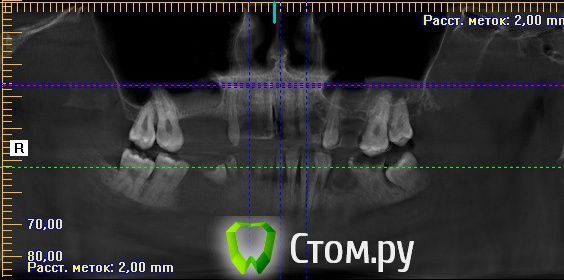

sergey765 Опубликовано 11 июня, 2014 Автор Поделиться Опубликовано 11 июня, 2014 посмотрите пожалуйста КТ. Ссылка на комментарий

sergey765 Опубликовано 11 июня, 2014 Автор Поделиться Опубликовано 11 июня, 2014 могу вам ещё снимков выложить.их довига. беспокаят меня боли после удаления .прошло 5 недель. снимки девушка лет 20 эти смотрела. сказала что у меня там инфекции дофига. типа давай я тебя на понедельник к хирургу запишу. он ранку вскроет. прочистит Ссылка на комментарий

Bier Опубликовано 11 июня, 2014 Поделиться Опубликовано 11 июня, 2014 это все не информативные кадры, в прикрепленных темах есть инструкция, выкладывайте КТ целиком, наш рентгенолог скачает и выложит срезы. 3 Ссылка на комментарий

sergey765 Опубликовано 12 июня, 2014 Автор Поделиться Опубликовано 12 июня, 2014 хорошо сейчас скидываю весь диск в рар архиве в файлообменник. люди добрые пожалуйста скачайте посмотрите. умоляю на коленях. ситуация у меня крайне серьезная. мне нужно чтобы хороший хирург посмотрел. в долгу не останусь. и если что у меня сильно там серьезное приеду к вам в клинику в москву/питер. а там что-то полюбас будет..... вчера когда делал КТ в частной клинике девочка (лет 20) смотрела, нифига вроде не поняла, сказала только у меня там инфекции полно (где там я не понял) и лунка удаленного зуба не заживает типа надо хирургу показать он вскроет прочистит т.е возможно когда мне зуб удаляли не прочистили там ничего... сейчас меня беспокоят боли в районе подбородка. самочувствие моё плохое. с кровати почти не встаю. все написано в начале данной темы.умоляю скачайте посмотрите. томограмма сделана программой iCATVision Ссылка на комментарий